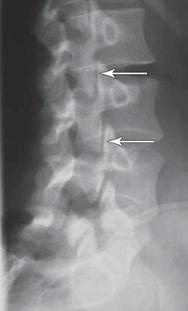

Рентгенограмма № 1. На снимке стрелкой указано расположение дугоотростчатых суставов позвоночника в состоянии нормы

Дугоотростчатые суставы осуществляют своеобразный контроль над движениями позвоночника. Например, они позволяют позвоночнику совершать движения, те же сгибание, разгибание, но в то же время ограничивают его движения в горизонтальной плоскости. Последнее позволяет при ротационных движениях позвоночника (от лат. rotatio — «кругообразное движение, вращение»), например при повороте туловища, при наклоне с поворотом, сохранять стабильное сочленение позвоночника и не проворачиваться позвонкам вокруг своей оси.